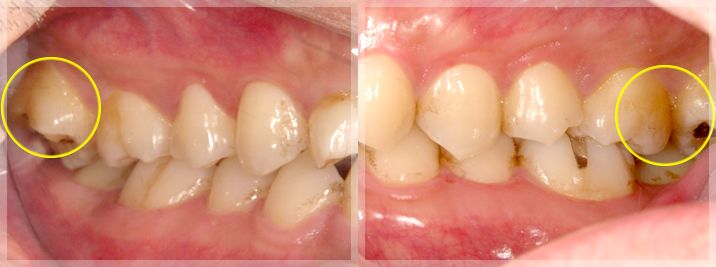

左の写真:咬合平面の乱れ|右の写真: 晩期残存乳歯

左右の写真:すれ違い咬合

すれ違い咬合の改善

咬合平面の乱れの改善